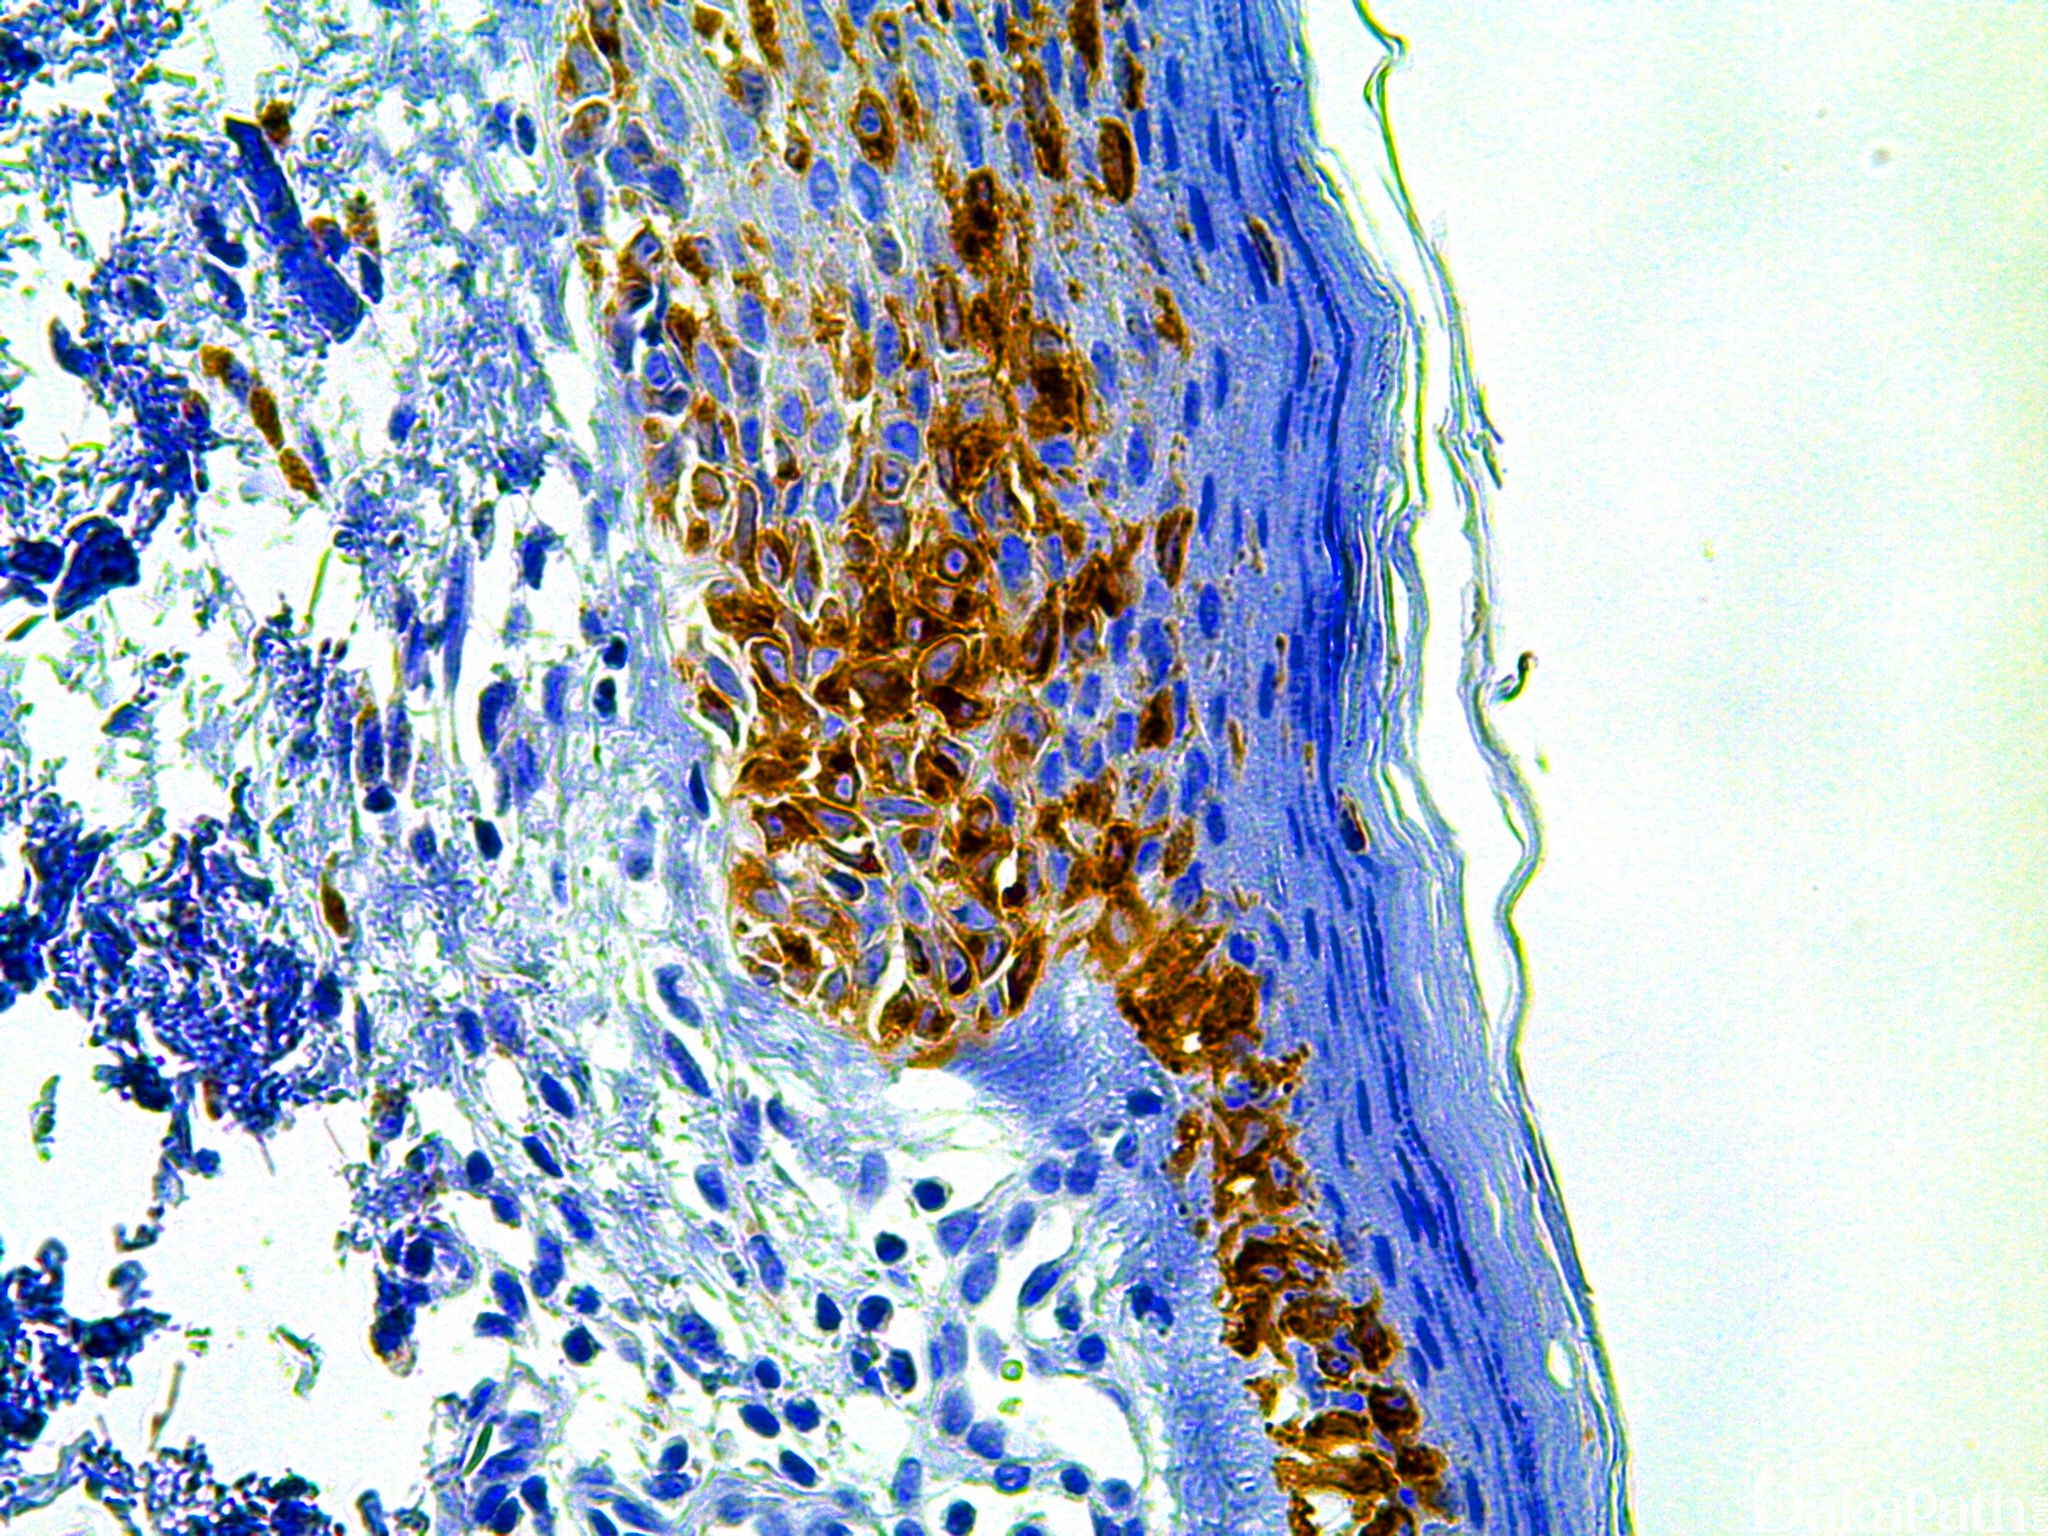

色素细胞特异性抗原,对色素合成及黑色素小体形成至关重要。

恶性黑色素瘤的诊断。

通常阳性(<95%,≥75%的病例阳性): 恶性黑色素瘤